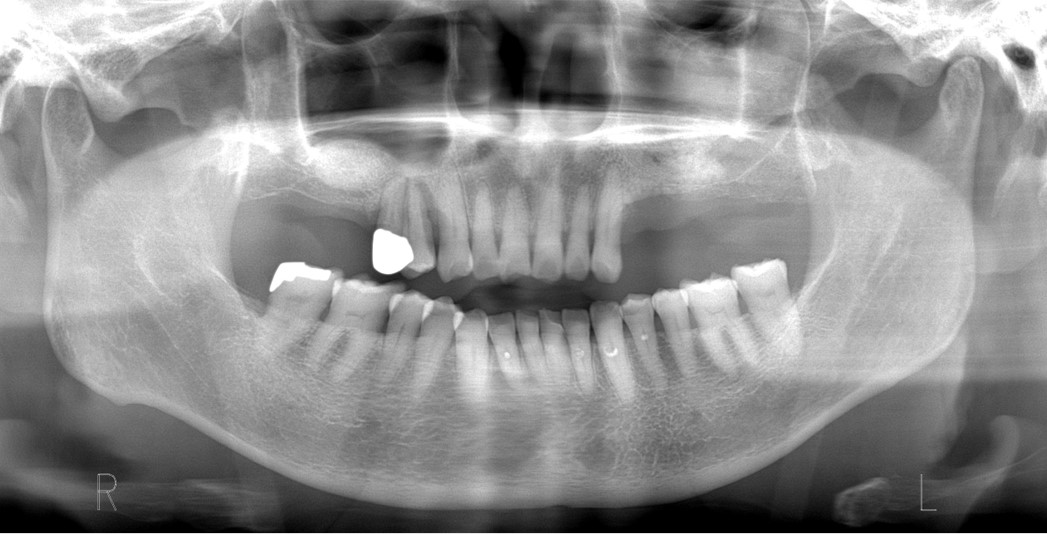

骨の形によっては、インプラントを埋入すると一部が口の中に露出することがあります。露出した部分をそのままにすると細菌が集まり、骨が吸収する原因となるので、露出した部分には人工骨などで覆い骨を作ります。先に人工骨で骨を作り、しっかりと骨ができた段階でインプラントを埋入することもあります。

インプラントを埋入すると部分的に露出したので人工骨で覆いました。